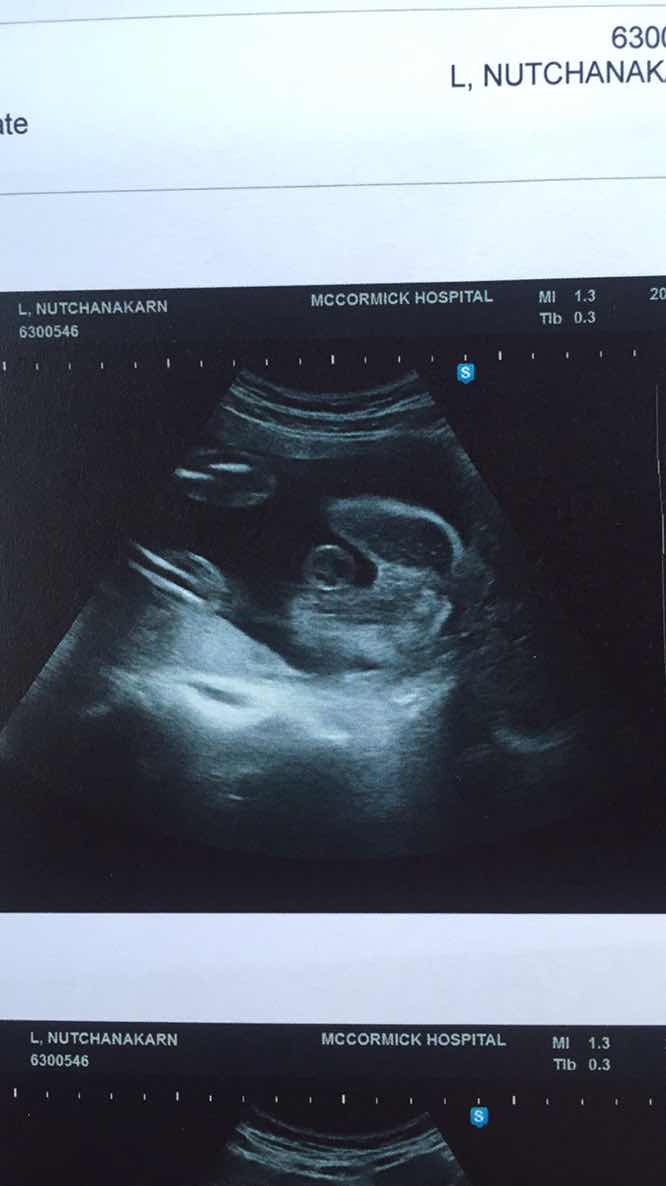

ขอดู รูปซาว หน่อยค่ะว่าเหมื่อนกันไหม หมอ บอกว่า เป็น ญ เพราะไม่มีจู๋โผลมา บ้านอื่น ได้ ญ แบบนี้หรือเปล่าค่ะ แม่แอบกังวล อยากได้ญ กลัว จู่ โผล่มาทีหลัง 😁23+4.

หมอบอกว่าได้ลูกผู้ชายน่ะค่ะ